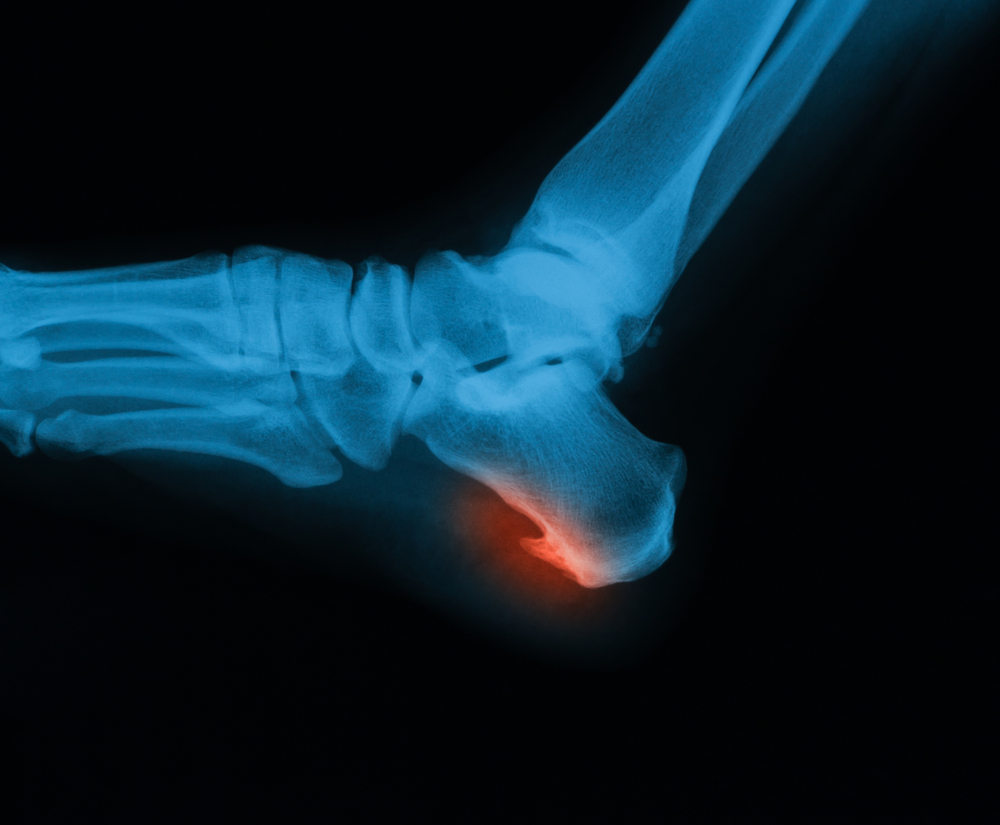

Врач обычно не испытывает затруднений при диагностике этой патологии. Предположить наличие пяточной шпоры он может, основываясь на жалобах пациента. Прощупать костный нарост обычно не удается, однако на рентгенограмме пяточной области всегда четко видны остеофиты. Если характерная боль в пяточной области при ходьбе есть, а на рентгеновском снимке изменения отсутствуют, то диагноз требует уточнения.